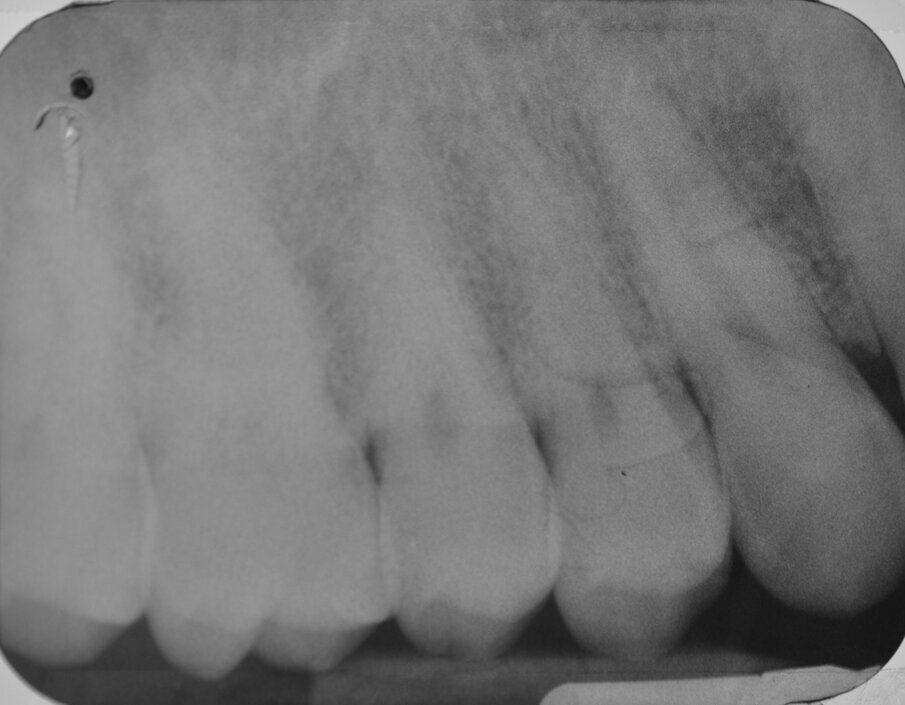

All’esame obiettivo viene si evidenzia una frattura verticale a carico dell’elemento in questione (Figg. 1, 2) che pone indicazione assoluta all’estrazione dentaria; per evitare di aggravare l’inevitabile contrazione della cresta ossea alveolare, si decide di eseguire l’estrazione dell’elemento fratturato senza sollevare alcun lembo. Viene effettuato un esame radiografico endorale allo scopo di visualizzare la morfologia della radice dentaria e i suoi rapporti con le strutture viciniori. (Fig. 3)

Fig. 3 - Esame radiografico endorale preoperatorio.